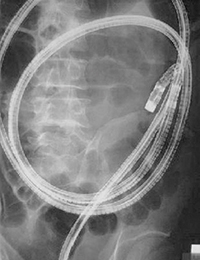

Принцип работы этой небольшой (размерами 26×11 мм и весом всего в 3,7 г) и поэтому вполне «удобоваримой» капсулы заключается в передаче высококачественных цифровых снимков тонкого кишечника на приемник, находящийся в поясе на теле пациента в течение всего исследования. Сама капсула состоит только из камеры, источника света, передающего устройства и занимающей больше всего места батареи, емкость которой позволяет, однако, сделать более 55 000 (!) снимков с частотой 2 снимка в секунду на протяжении 6 ч, чего оказывается, как правило, вполне достаточно для составления целостной картины обо всем тонком кишечнике. Естественно, что такое количество снимков сначала анализируется соответствующей компьютерной программой и уже ее результаты в виде «короткометражного» фильма оценивает гастроэнтеролог.

В литературе отмечают очень хорошую переносимость исследования пациентами, что делает его доступным даже в педиатрической практике (в таком случае, правда, капсула вводится в желудок эндоскопическим путем). Взрослый пациент без особых проблем глотает капсулу, запивая ее стаканом воды. Единственным однозначным противопоказанием для капсульной эндоскопии является наличие доказанных выраженных стенозов кишечника; пока что нерешенным остается и вопрос о безопасности этого исследования у пациентов с водителями ритма сердца и дефибрилляторами, а также применение этой методики у беременных — пока что недостаточно исследований, чтобы сделать однозначные выводы по этим вопросам.

Понятно, что применение этой методики противопоказано и пациентам как с манифестной кишечной непроходимостью, так и хроническими нарушениями моторики кишечника, в частности диабетической гастроэнтеропатией. Другим относительным «противопоказанием» является достаточно высокая стоимость исследования, составляющая 1000–1300 евро, из которых большая часть (около 600 евро) приходится непосредственно на саму капсулу. А основными ее недостатками являются отсутствие возможности управлять исследованием (как следствие, наличие «слепых участков» и отсутствие по-настоящему целостной картины тонкого кишечника) и невозможность проведения биопсии и осуществления

эндоскопических вмешательств на патологических участках кишки. Несмотря на это, капсульная эндоскопия на Западе успела даже за такой короткий промежуток времени завоевать широкое признание со стороны гастроэнтерологов, эндоскопистов и хирургов. Только в Германии этой методикой пользуются специалисты в более чем 200 гастроэнтерологических клиниках, а общее количество проведенных во всем мире капсульных эндоскопий уже превысило 150 000!